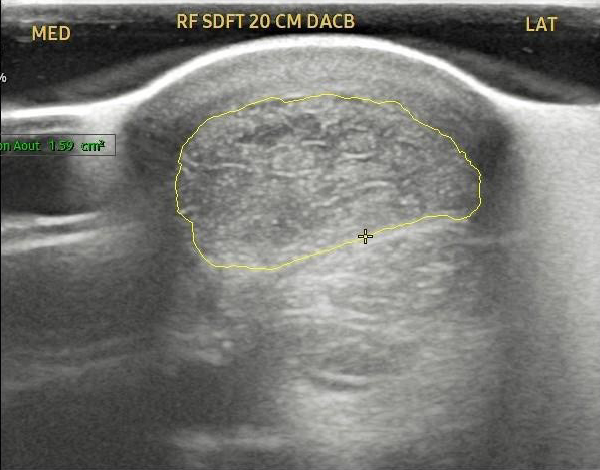

Case Study 2 – Equine Tendon Regeneration

The attached images show a pre- and post-treatment equine superficial digital flexor tendon injury.

This horse received two injections spaced one month apart and at the 2 ½ month point has produced a reduction in the core tendon lesion of approximately 70%.

Source: Temecula Creek Equine